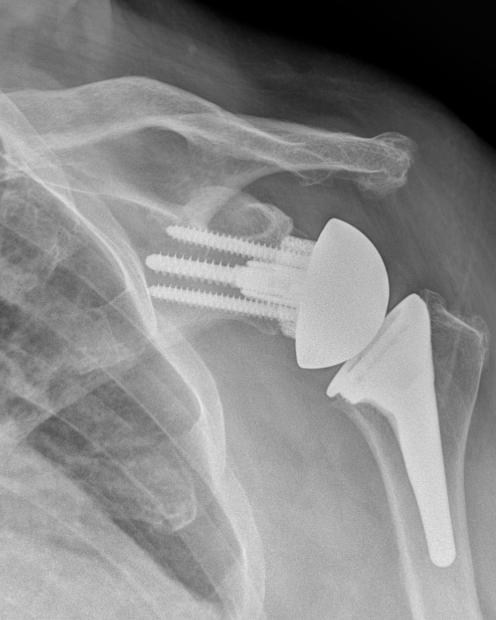

By Yuri Lewicky, M.D.

The human body has an incredible ability to heal. Yet, with age, repetitive use or injury, that healing capacity has limits. While avoiding surgery is always preferable, modern shoulder medicine offers excellent solutions when surgery becomes necessary.

WHEN SHOULDER REPLACEMENT

SURGERY IS THE BEST OPTION

Surgery may be the right choice when pain and stiffness persist despite therapy and medication. There’s no need to suffer. Shoulder replacement has advanced dramatically, offering implants tailored to each patient and condition. Outcomes are better than ever.

TWO SURGICAL OPTIONS

There are two surgical options for shoulder arthritis: Partial shoulder replacement (hemiarthroplasty) and total shoulder replacement (anatomic).

The goal of these surgeries is to reestablish near normal anatomy. The worn-out parts of the shoulder joint are replaced with a custom metal implant on the arm bone (humeral side) that matches your normal anatomy. A stemless design (absence of a long metal rod in the bone) or a stemmed implant is utilized. Stemless designs preserve bone and are less invasive but require good bone quality.

With a partial shoulder replacement, the socket side of the joint (glenoid) is either left alone or symmetrically reamed to create a stable surface. Utilization of this is normally reserved for very young individuals.

In an anatomic design, the socket is replaced with a plastic component called a “poly”

recreating joint spacing and normalizing the shoulder’s center of rotation.

The reverse total shoulder brought on a surgical revolution with its introduction into the U.S. in 2002. It has been a breakthrough for complex problems such as irreparable rotator cuff tears, severe bone loss, fractures, and failed prior surgeries. This type of surgery is an anatomy altering procedure in which it reverses or flips the normal anatomy, the native head of the joint becomes the socket, and the native socket becomes a head.

Shoulder replacement is not just about showing up for surgery; it’s a team effort between patient and the surgical team.

Key personal considerations include:

Have you exhausted conservative care?

Were your imaging studies (X-ray, CT, MRI) thoroughly reviewed? Bring copies to every appointment.

Have you completed dental, medical and infection screenings?

Does the team offer postoperative multimodal pain control and ultrasound-guided nerve blocks?

Is outpatient surgery an option?

Which implant is recommended and why?

Is there an emphasis on surgical precision?

Do you trust and feel comfortable with your surgical team? (Never hesitate to seek a second opinion.)

KEY TECHNICAL CONSIDERATIONS

INCLUDE:

Preservation of key muscles, such as the